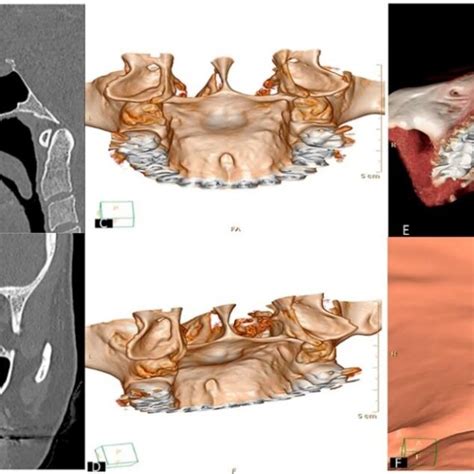

- Torus palatino: Si notas un bulto duro en el centro del paladar, es muy posible que se trate de un torus palatino. El torus es básicamente un crecimiento excesivo de hueso en el paladar duro. Suele aparecer en la línea media del paladar y tiene una consistencia ósea (firme al tacto). No duele ni crece rápidamente, más bien se desarrolla lentamente a lo largo de los años. Mucha gente convive con un torus palatino sin darse cuenta, ya que suele ser asintomático y benigno. De hecho, se considera una variante anatómica normal en un porcentaje de la población.